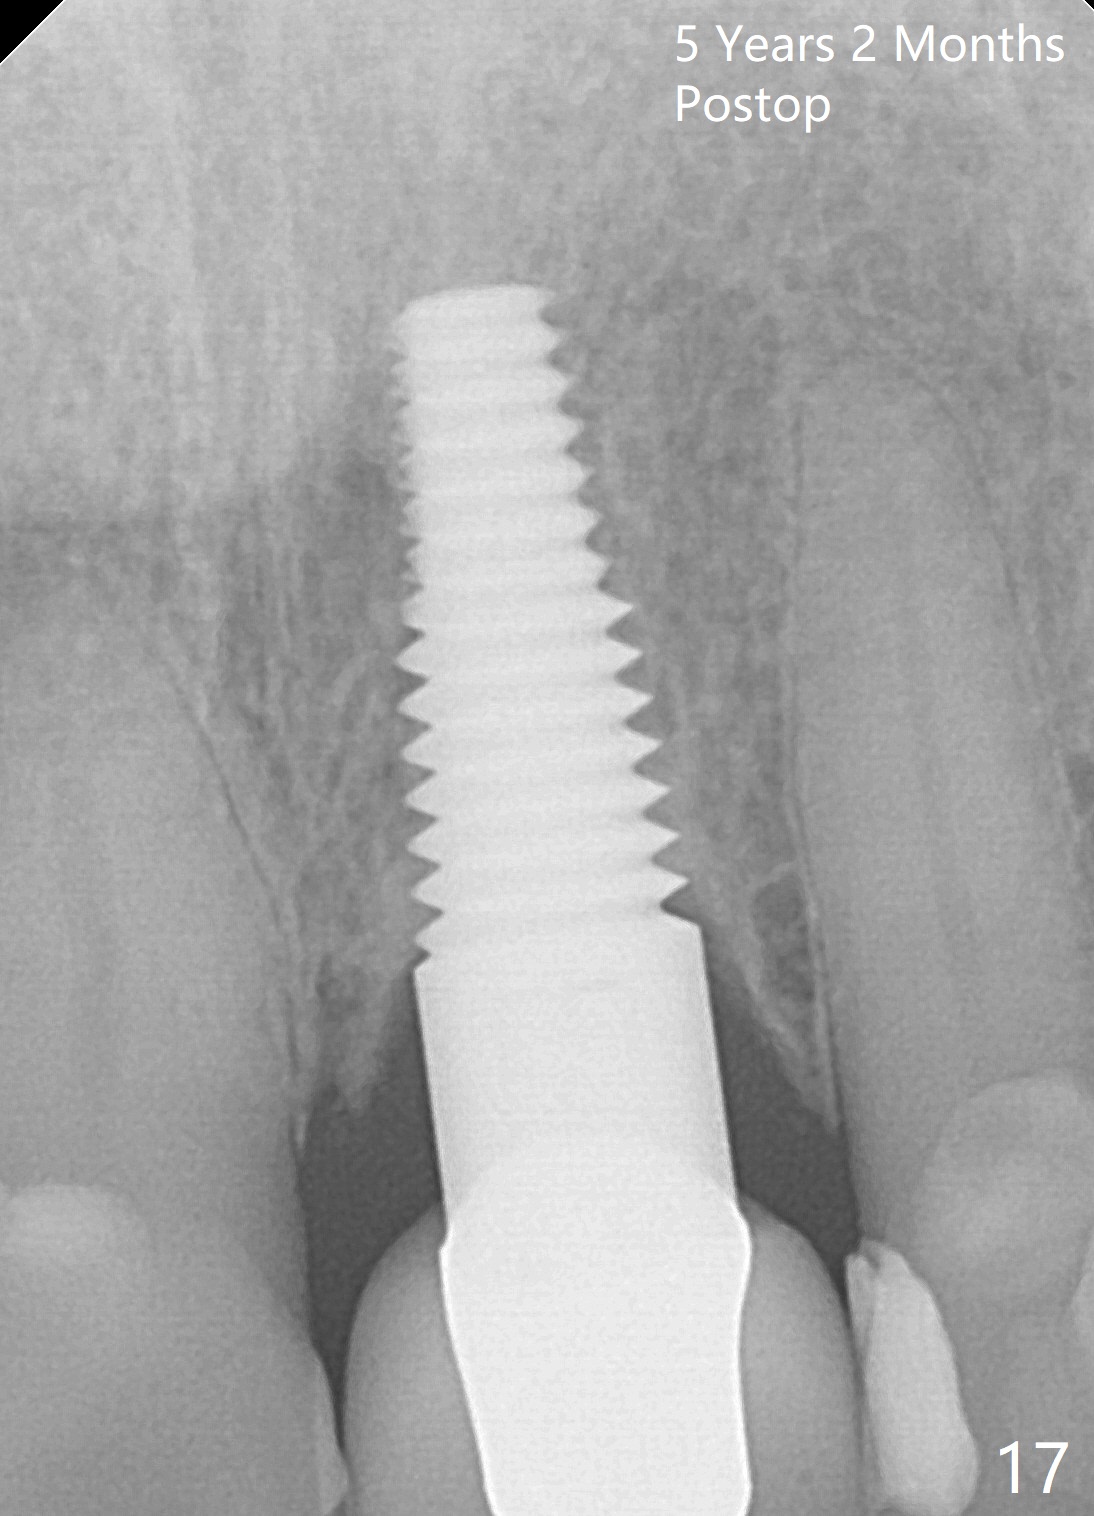

Although there is no bone loss around the implant (Fig.17), metal starts to show 5 years 2 months postop (Fig.18 ^), probably related to the buccal placement, too large the implant for the site or buccal plate atrophy (Fig.19).